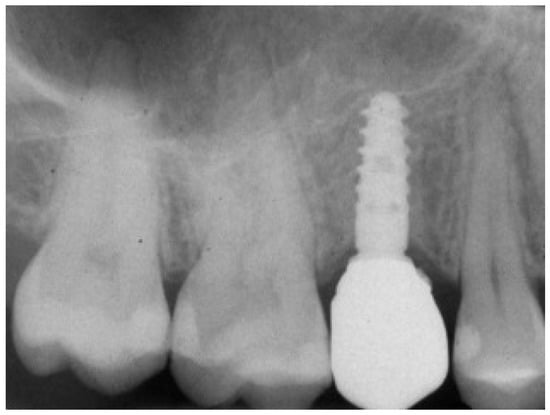

Figure 10.

Post-surgical rx control of the implant and healing abutment.

At 1 year year after placement, all 36 implants were regularly functioning, for a survival rate of 100% (36/36 implants surviving) (Figure 15).

Figure 15.

One-year follow-up rx control of the implant supported crown.